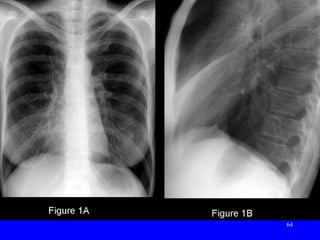

57 Pneumococcal pneumoniaPneumococcal pneumonia Rupper lobe consolidation with Air BronchogramR upper lobe consolidation with Air Bronchogram

• #65 Fig. 1A: CXR: ill-defined R perihilar opacity obscuring R heart border and contains no air bronchograms. Lateral XR: Fig. 1B: a corresponding triangular opacity with its base abutting the sternum and its apex directed toward hilum. Note anterior displacement of oblique fissure and elevation of R hemi-diaphragm. Dx: : R Middle Lobe Atelectasis (Endobronchial Sq Cell Lung Ca)